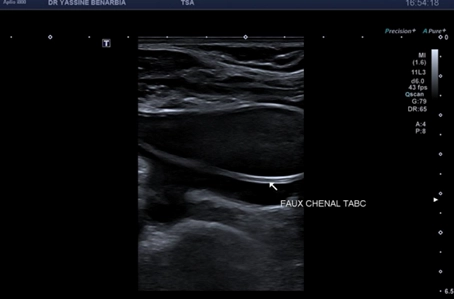

Quand des "tendinopathies achilléennes" cachent un piège poplité : l’importance de l’échographie dynamique et de l'examen clinique concomitant

27/02/2026